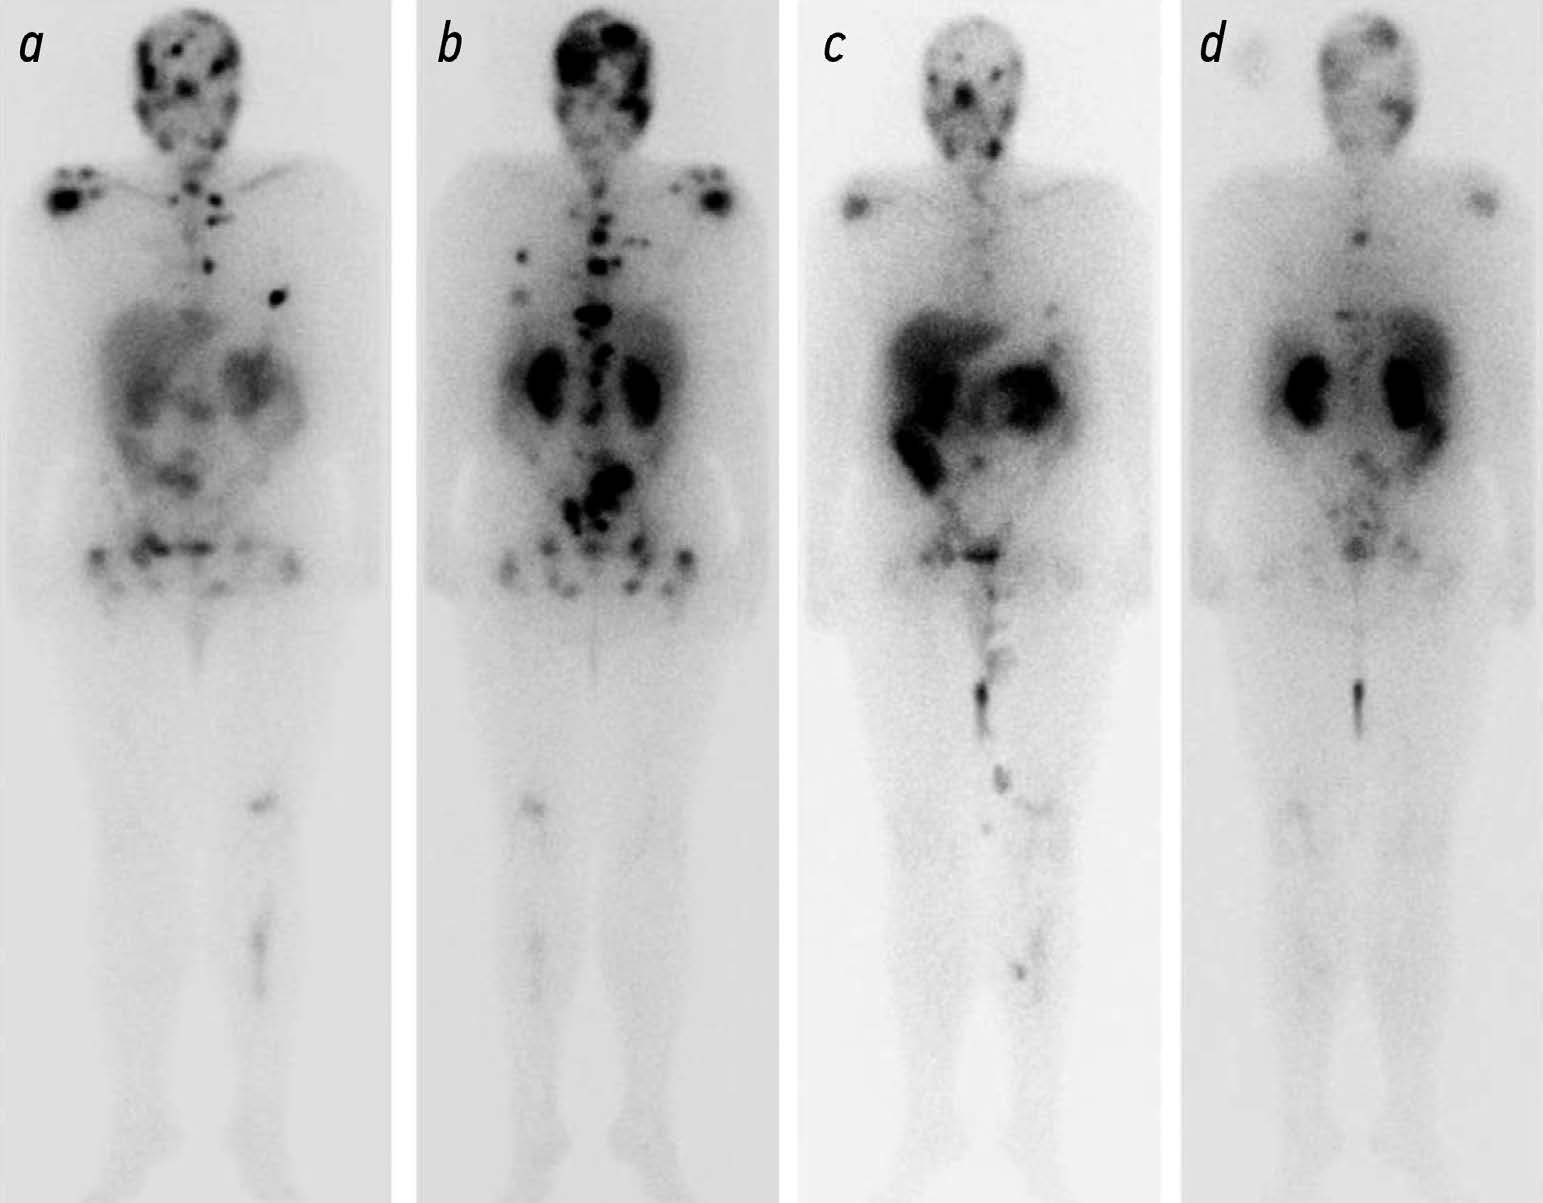

Potential use of radiation methods for diagnosing bone metastases of castration-resistant prostate cancer: a literature review

Metastatic castration resistant prostate cancer (mCRPC) is the tumor progression with the development of resistance to androgen deprivation therapy. The incidence of bone metastases in these patients reaches 90%. Radiology is widely used to diagnose mCRPC. Computed tomography (CT) and magnetic resonance imaging (MRI) are beneficial in anatomic imaging, but have some limitations in evaluating effectiveness of disease treatment. Scintigraphy is used to screen for bone metastases, but is poorly suited for assessing disease progression. Positron emission tomography (PET) combined with CT and single photon emission CT are used for early detection of local or systemic spread of prostate cancer. PET of prostate specific membrane antigen is used to predict the effectiveness of anti tumor therapy based on the absorbed dose of a radiopharmaceutical (RP). The introduction of RPs (177Lu-PSMA) opens up new perspectives for radionuclide therapy with simultaneous evaluation of its efficacy using hybrid visualization. The potential use of radiology in the diagnosis of bone metastases is of particular interest for the analysis and systematization of the data obtained and for the development of indications for radioligand therapy and the evaluation of its efficacy.

Published data indicate that radiologic modalities for the diagnosis of mCRPC vary in sensitivity and specificity and have their own advantages and limitations, so these modalities should be combined.

The development and improvement of methods to quantitatively assess treatment efficacy and identify prognostic markers will enable more informed selection of treatment strategies and radiopharmaceuticals, leading to improved overall survival.